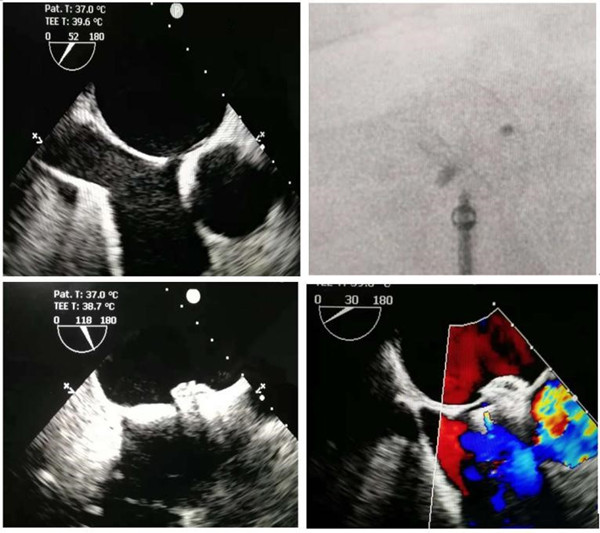

術(shù)中TEE測(cè)量心耳大?。?span lang="EN-US">

0度 20mm 45度 22mm 90度 22mm 135度 20mm

DSA測(cè)量心耳開口25 mm,深度25 mm

根據(jù)TEE及DSA測(cè)量的結(jié)果,綜合考慮后,選用30mm WATCHMAN左心耳封堵器,封堵傘展開后,測(cè)量計(jì)算壓縮比為26%,牽拉穩(wěn)定,滿足PASS原則,釋放器械,成功封堵。

房缺(ASD)封堵術(shù):TEE及DSA下封堵房間隔

房缺封堵器與左心耳封堵器DSA下顯影